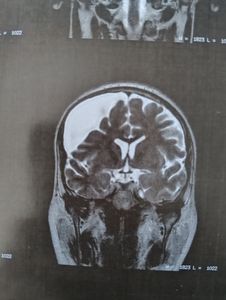

Cirurgia cérebral, a um ano na espera do SUS, mas sem sucesso, perca da visão do lado direito devido a compressão da massa.

Massa cerebral em crescimento, dores diariamente, já perdeu a visão direita toda praticamente.